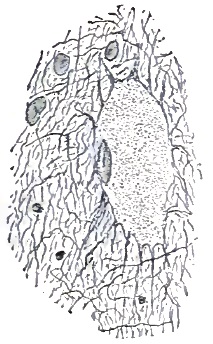

| 43. | FLAT GLIOMA-CELL WITH ITS FIBRILLAR CONNECTIONS (OSLER) |

| 44. | HOMOGENEOUS TRANSLUCENT FIBRE-CELL (OSLER) |